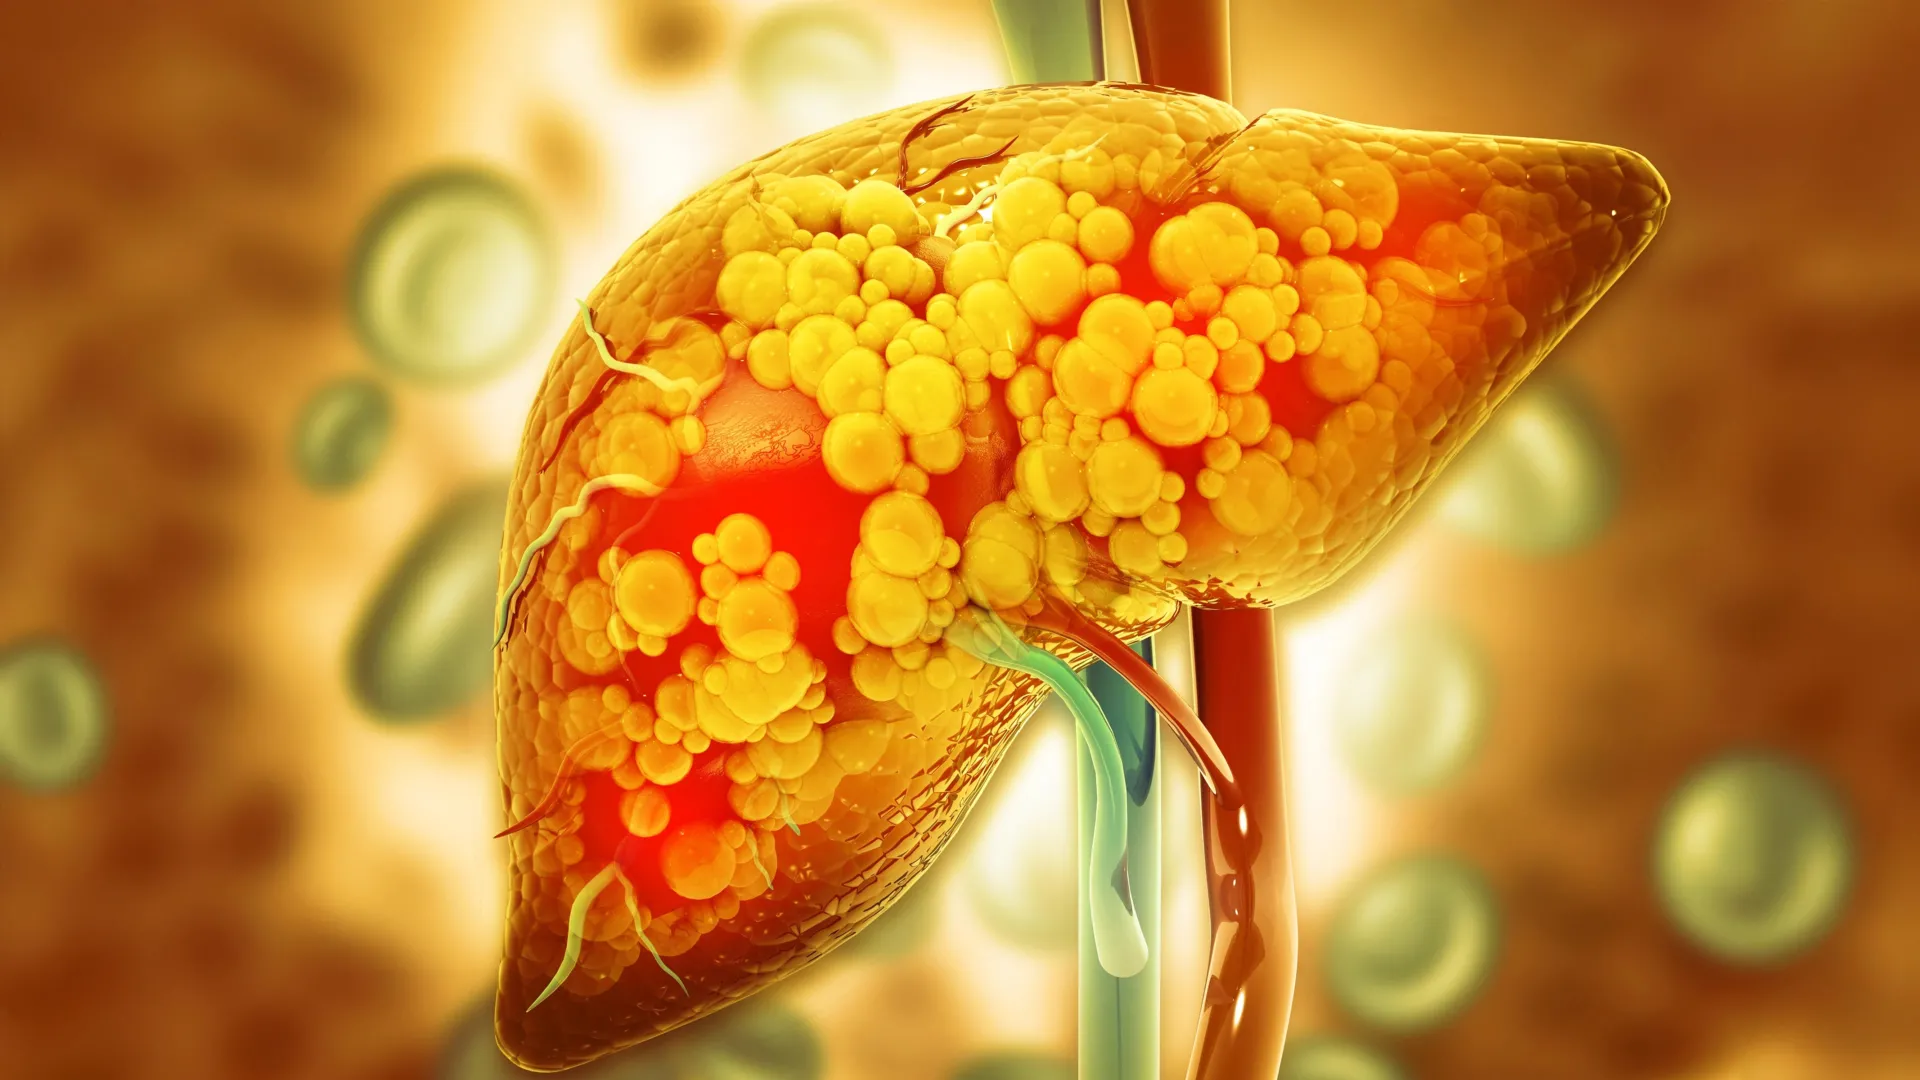

The global health landscape faces a formidable challenge in the escalating prevalence of metabolic dysfunction-associated steatotic liver disease (MASLD), a condition formerly recognized as non-alcoholic fatty liver disease (NAFLD). This hepatic disorder, characterized by excessive fat accumulation in the liver, is no longer confined to the adult population; it is increasingly diagnosed in children, often with a more aggressive trajectory. A significant contributing factor to this concerning trend has been identified as maternal dietary patterns during critical periods of gestation and lactation, particularly those characterized by high caloric density from fats and refined sugars. However, pioneering research emanating from the University of Oklahoma now offers a glimmer of hope, suggesting a novel mechanism through which this intergenerational vulnerability might be attenuated. A recent investigation revealed that offspring born to pregnant and nursing mothers, when supplemented with a naturally occurring compound generated by beneficial gut microbiota, exhibited markedly reduced rates of MASLD as they matured.

At the heart of this transformative discovery lies indole, a small organic molecule that emerges as a byproduct of tryptophan metabolism by specific bacterial species residing within the gut. Tryptophan, an essential amino acid, is widely available in protein-rich foods such as poultry and various nuts. The findings of this study significantly augment the burgeoning body of scientific literature dedicated to understanding and ultimately preventing MASLD, a condition inextricably linked with metabolic syndrome and type 2 diabetes. While MASLD afflicts individuals across all age demographics, its progression in pediatric populations is often accelerated, posing a substantial long-term health burden.

The profound metabolic benefits observed in the offspring born to mothers who received indole supplementation were multifaceted and strikingly persistent. These progeny exhibited significantly improved markers of hepatic health, evidenced by macroscopic and microscopic evaluations of liver tissue. Beyond the liver, these mice displayed a reduced propensity for weight gain, maintained more stable and lower blood glucose concentrations, and developed adipocytes (fat cells) of notably smaller dimensions, even when subsequently exposed to an unhealthy, obesogenic diet during their adult lives. These systemic improvements strongly suggest a broader positive impact on metabolic regulation. Furthermore, the researchers identified the activation of a critical protective signaling cascade within the gut involving the acyl hydrocarbon receptor (AHR). The AHR is a ligand-activated transcription factor expressed in various tissues, including the gut and liver, known to play diverse roles in detoxification, immune regulation, and maintaining intestinal barrier integrity. Its activation by indole suggests a potential mechanism by which the compound exerts its beneficial effects, perhaps by enhancing gut barrier function, reducing inflammation, or directly influencing hepatic lipid metabolism.

Further granular analysis of lipid profiles within the liver yielded additional insights into indole’s protective mechanisms. The study revealed no discernible increase in the accumulation of detrimental long-chain ceramides, a class of lipids strongly implicated in insulin resistance, cellular stress, and programmed cell death (apoptosis) in the context of metabolic dysfunction. Conversely, levels of beneficial very long-chain ceramides were observed to rise. This shift in ceramide species suggests a favorable alteration in lipid metabolism, moving away from pro-inflammatory and pro-apoptotic pathways towards those associated with healthier cellular function. Ceramides, as sphingolipids, are crucial components of cell membranes and act as signaling molecules, influencing a wide array of cellular processes. The differential regulation of their chain length by indole highlights a sophisticated metabolic reprogramming effect.